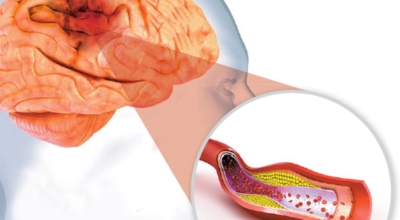

뇌졸중은 뇌경색과 뇌출혈 두가지로 나뉘게 돼요. 먼저 뇌경색은 뇌혈관이 막혀 영양분과 산소를 주는 피가 통하지 않는 상태로 원은은 크게 세 가지로 나눌 수 있는데요 동맥경화증이 생겨 좁아진 부위로 인하여 혈액공급이 부족해지거나 좁아지다가 결국 막혀버리는 경우, 큰 혈관에서 분지한 작은 혈관들이 고혈압 등으로 압박을 받으면 혈관이 막히는 경우가 있습니다.

육체의 혈액순환을 방해하는 모든 까닭이 뇌졸중의 까닭이 될 수 있답니다. 흡연과 음주 또한 뇌졸중의 까닭이 될 수 있다고 하며 고혈압, 당뇨, 비만, 고지혈증 또한 뇌의 혈액순환을 방해하고 뇌혈관 건강을 악화시키만드는 이유가 되는 것 중 1개로 보고 있답니다.

옳지 않은 식습관 또한 뇌 혈관 건강을 망치는 위험인자로 보고 있는데 맵게 먹거나 짜게 먹거나 채소류를 잘 섭취하지 않고 지방이 많은 고기를 주로 먹고 과식과 폭식을 한다면 뇌혈관 건강을 망치는 주범이 될 수 있습니다. 또한 운동 부족과 스트레스도 뇌졸중의 이유가 되는 것이 될 수 있답니다.